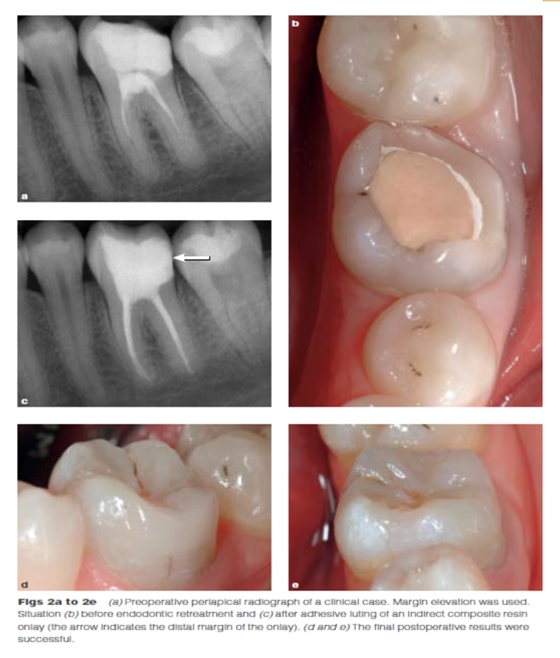

DME是用一個(gè)改良彎曲的成型片接堆放復(fù)合樹(shù)脂來(lái)提升齦壁高度,使其能夠在修復(fù)過(guò)程中使用橡皮障封閉邊緣,可以在固化前適當(dāng)?shù)囊瞥嘤嗟膹?fù)合樹(shù)脂。DME應(yīng)該在即刻牙本質(zhì)封閉(IDS)之后,在使用橡皮障的條件下,且僅在邊緣可被改良的成型片適當(dāng)隔離時(shí)直接獲得。否則,這個(gè)技術(shù)不能使用。在最終取印前,需要拍攝咬合翼片來(lái)評(píng)估復(fù)合樹(shù)脂在齦邊緣區(qū)域的密合度(有無(wú)懸突或缺陷)。同樣需要仔細(xì)隨訪來(lái)評(píng)估軟組織的健康和是否需要外科手術(shù)干預(yù)。只要可能,在牙髓治療前就應(yīng)通過(guò)DME術(shù)制造假壁,使根管治療更完善(圖2、3)。圖4展示了一個(gè)典型DME術(shù)的適應(yīng)癥。

Dietschi和Spreafico在1998年提出了另一種方法,即在間接修復(fù)體的下面放置一個(gè)復(fù)合樹(shù)脂基底來(lái)取代冠向提升邊緣(圖1)。這個(gè)方法即我們所知的齦壁提升術(shù)(DMG)是在橡皮障隔離下完成的?(This procedure,…,is performed under rubber dam isolation following the placement of a matrix.)如今,DME(齦壁提升術(shù))通常與IDS(即刻牙本質(zhì)封閉術(shù))聯(lián)合使用來(lái)促進(jìn)間接粘接修復(fù)體的粘接和齦邊緣的封閉。此外,邊緣的齦上提升,粘接復(fù)合樹(shù)脂基底被用于封閉牙本質(zhì)、加強(qiáng)潛在牙尖?(reinforce undermined cusps),充填倒凹(fill undercuts),以及為嵌體/高嵌體修復(fù)提供必要的幾何形態(tài)。